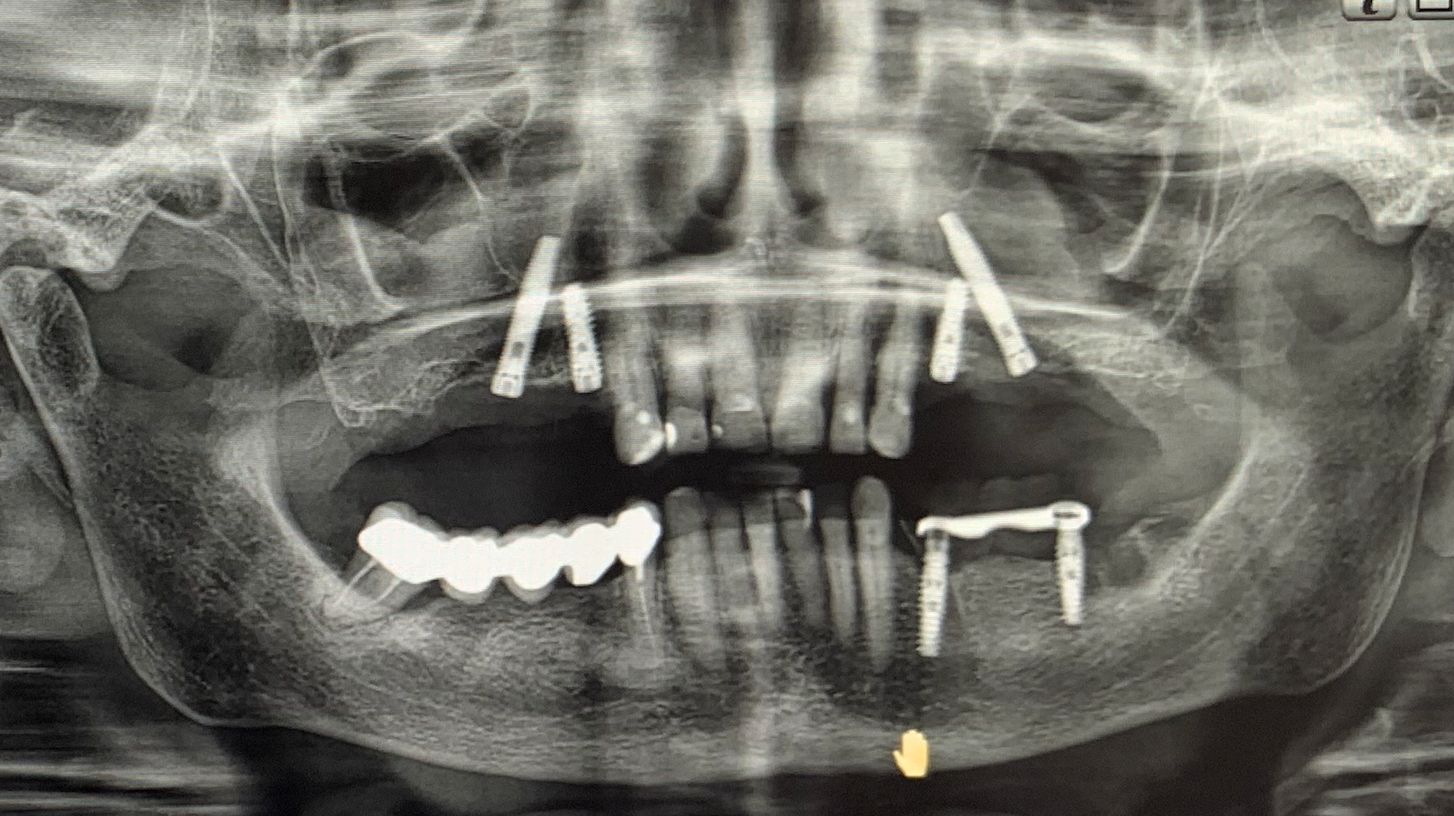

A seguito di un'accurata valutazione clinica e radiografica preparatoria (Fig. 1) è stato pianificato l'inserimento di impianti IS+ (BTK) nelle regioni anteriori e di impianti BT-Rhyno (BTK) nei settori posteriori mediante tecnica transinusale.

Fig. 1 - Valutazione clinica e radiografica preoperatoria

L'intervento è stato completato in un'unica seduta chirurgica, adottando un approccio minimamente invasivo e nel pieno rispetto dei tessuti. Le immagini intraoperatorie illustrano chiaramente le principali fasi del trattamento: il posizionamento degli impianti anteriori IS+, l'inserimento transinusale degli impianti BT-Rhyno e l'applicazione di osso autologo per la rigenerazione finale (Fig. 6).

Fig. 6 - Immagini intraoperatorie